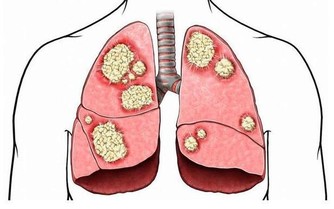

股骨頭壞死是導致胯骨疼痛的一個重要原因,發生率約佔胯骨疼痛的20%。它是指股骨頭骨細胞因血液供應不足而逐漸死亡,最終導致骨頭結構損壞的一種病理過程。

特發性較多見,主要與個體血液供應不良等先天因素相關。繼發性則常由創傷、使用荷爾蒙、酗酒等導致。無論何種原因,都會使骨頭微循環阻塞,造成局部缺血壞死。

病程初期可出現活動後疼痛,休息後緩解。隨著壞死面擴大,胯部疼痛會加劇,持續壓痛,休息後不會緩解,嚴重影響生活。透過檢查可見X光股骨頭密度降低、塌陷。對於這種疾病的治療,專家建議以保守治療為主,也可依年齡選擇人工關節置換。

而預防股骨頭壞死的關鍵在於確保股骨頭的良好血液供應。中老年人應多進行適度運動,增強心肺功能,並控制脂肪肝等。同時避免外傷,不濫用藥物和酒精。另外,發現早期症狀,及時治療也很關鍵。要知道,股骨頭壞死若處理不當,最終可使髖關節功能完全喪失。